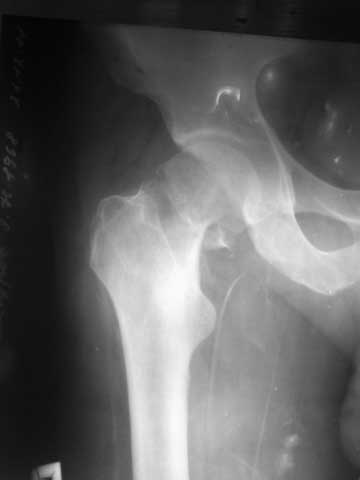

Уважаемые коллеги! Очень уважаемый наш коллега из далекой области по телефону отправил р-снимок своего брата, 43года, с переломом шейки бедра.

Снимок не очень качественный, пока других нет,кажется перелом субкапитальный, линия излома косая, похоже В2,2 по АО,или Паувельс- 2,. Просит, если можно, чтобы наш форум помог советом, каким способом лечить брата.